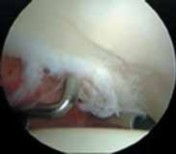

TECHNIQUES A B TECH FIG 1 • Arthroscopic view of a right hip from the anterior portal. A. A fragmented labral tear with degeneration within its substance is identified. B. Débridement is initiated with the power shaver. C. A portion of the comminuted labral tear is conservatively stabilized with a radiofrequency probe. D. The damaged portion has been removed, preserving the healthy substance of the C D labrum. LABRAL REPAIR